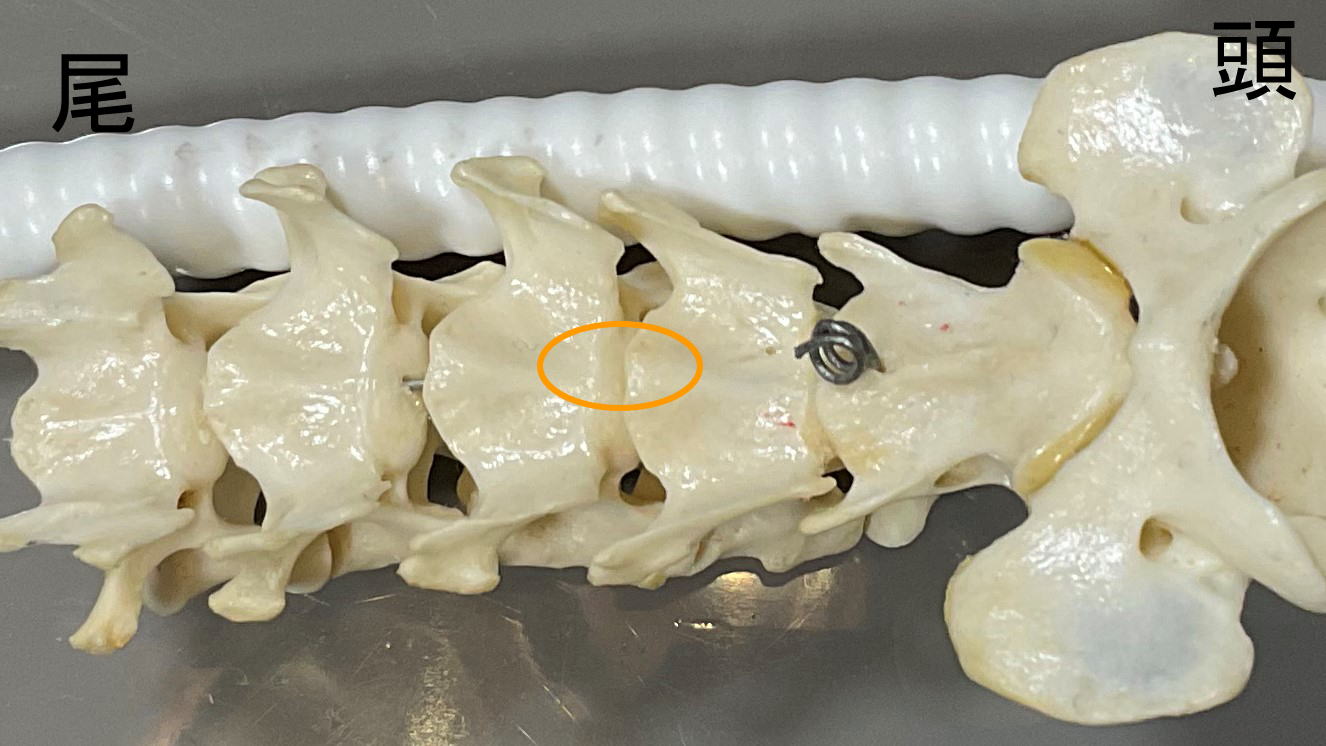

気管などの臓器を除けて、椎体の腹側を削っていきます

頸椎模型:オレンジ丸部分を削っています